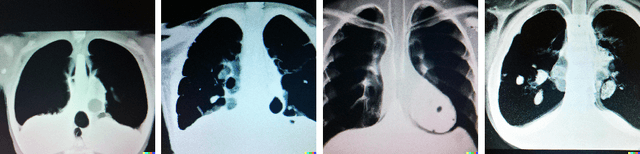

Abstract:Generative models are becoming popular for the synthesis of medical images. Recently, neural diffusion models have demonstrated the potential to generate photo-realistic images of objects. However, their potential to generate medical images is not explored yet. In this work, we explore the possibilities of synthesis of medical images using neural diffusion models. First, we use a pre-trained DALLE2 model to generate lungs X-Ray and CT images from an input text prompt. Second, we train a stable diffusion model with 3165 X-Ray images and generate synthetic images. We evaluate the synthetic image data through a qualitative analysis where two independent radiologists label randomly chosen samples from the generated data as real, fake, or unsure. Results demonstrate that images generated with the diffusion model can translate characteristics that are otherwise very specific to certain medical conditions in chest X-Ray or CT images. Careful tuning of the model can be very promising. To the best of our knowledge, this is the first attempt to generate lungs X-Ray and CT images using neural diffusion models. This work aims to introduce a new dimension in artificial intelligence for medical imaging. Given that this is a new topic, the paper will serve as an introduction and motivation for the research community to explore the potential of diffusion models for medical image synthesis. We have released the synthetic images on https://www.kaggle.com/datasets/hazrat/awesomelungs.